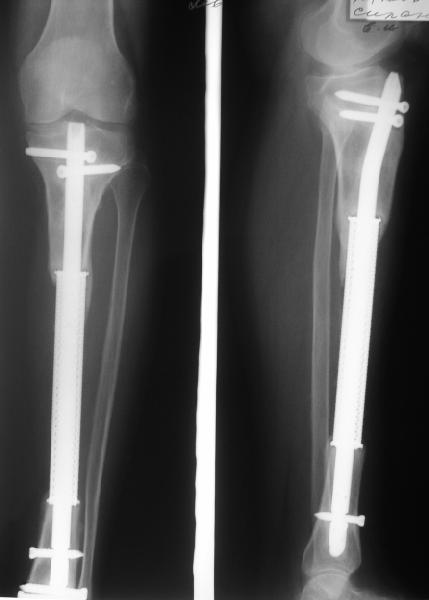

В настоящее время целостность мягких тканей голени полностью восстановлена, кожные лоскуты на мышце розовые фиксированные, раны закрыты на 100%, больной активен, ходит на костылях с дозированной нагрузкой на ногу в аппарате. Планируем выписать его на месяц по месту жительства. И если не получится с Минском, сделаем ему как и планнировали что-то вроде операции Гана-Кодивилла-Геттингтона. Пациент заранее настроен на длительное лечение в аппарате Иллизарова, уже хорошо адаптирован,оптимистичен и пока очень доволен результатами, отмечает значительное улучшение самочувствия. В приложении высылаю фотографии рентгенограм до и после операции.

В приложении рентгенограмма через год после операции.